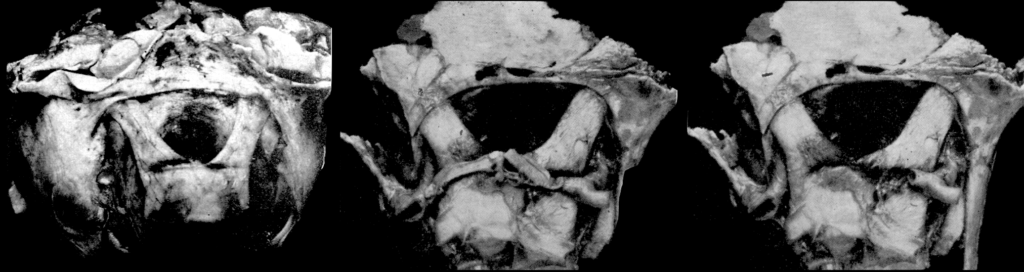

Left: Case 1 – Large pituitary tumour. Passing transversely across the anterior portion of the chiasm is a notch cut by the anterior cerebral and communicating arteries.

Middle: Case 2 – Chiasmal region at authopsy.

Right Case 2 – removal of anterior cerebral arteries to reveal notching of the chiasm. Rucker and Kernohan 1953

The Rucker and Kernohan study offered systematic clinicopathological correlation using autopsy material, visual fields, and detailed anatomical mapping. Their work demonstrated that these arterial notches can mimic or contribute to bitemporal hemianopia and other visual deficits, particularly in late-stage pituitary tumours. This optic variant of Kernohan’s notch remains an important differential consideration in neuro-ophthalmology, although rarely emphasized in modern texts.